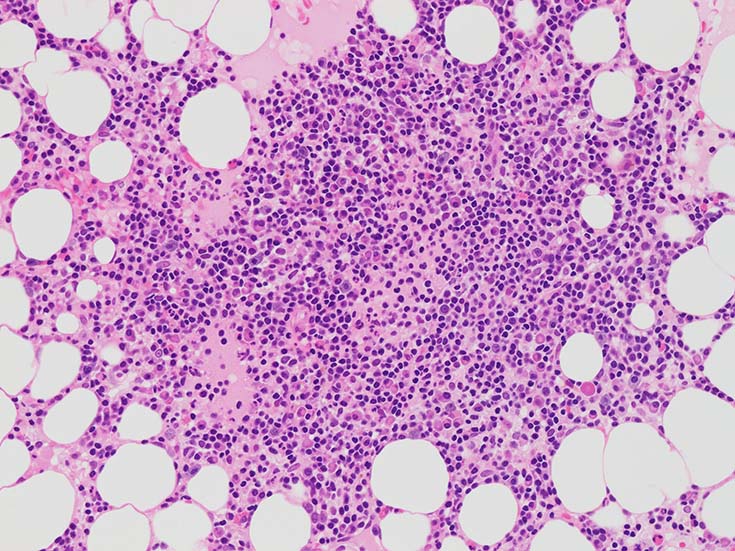

Bone marrow clot sectionでは, nodularな病変形成が認められる. HEでは不明瞭であるが, Naphtol-ASD-CAE-Giemas染色では mast cellの顕著な増加が明瞭に認識される.

明瞭な結節が形成されず,造血細胞内に小さなクラスタを形成して散在する場合もある.

増殖するB細胞はCD19+, CD20+. 結節内に増加する形質細胞はCD19+, CD20‐である. (多発性骨髄腫の形質細胞様細胞はCD19陰性).~  多くのB細胞がMUM1陽性を示す. CD5, CD10, BCL6は陰性.